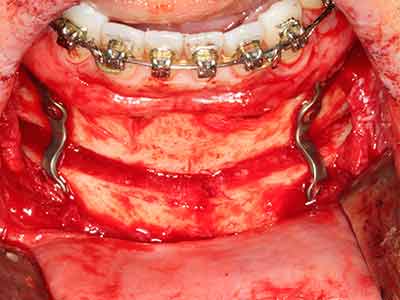

Indication: Bone splitting

Bone tissue is not simply a mineral structure but also contains a substantial proportion of collagen fibres. This means it not only has good compressive strength but also a degree of flexibility, which can be taken advantage of when performing bone augmentations. In the classical expansion procedure using bone splitting, the atrophied alveolar ridge is split longitudinally and carefully expanded after reaching an adequate osteotomy depth (Fig. 13-16), ideally without substantial removal of the periosteum (Brugnami, Caiazzo et al. 2014, Stricker, Fleiner et al. 2014). Screw and plate systems with increasing expansion distance have proven effective in separating the two bone lamellae while remaining below the fracture threshold. In general, residual bone widths of at least 3–4 mm are required (Chiapasco, Zaniboni et al. 2006) to guarantee adequate flexibility and sufficient bone coverage of the future implants. If necessary, a vertical relief osteotomy on one or both sides can improve flexibility. A combination with additional augmentation techniques, particularly on the buccal side, has been described as an alternative to the classical technique.

The splitting procedure is particularly atraumatic and there is no significant loss of dimension when using piezosaws, and there are no significant differences between implants in split jaws and implants in an alveolar ridge without a bone deficit (Chiapasco, Zaniboni et al. 2006, Danza, Guidi et al. 2009). However, sufficient continuous irrigation is essential, particularly with locally restricted and deep splitting to prevent thermal stress in the apical osteotomy regions.